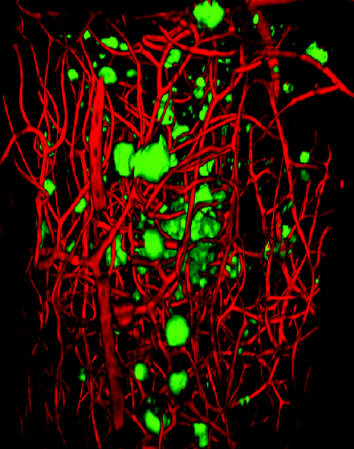

Marko Repic and Madeline A. Lancaster